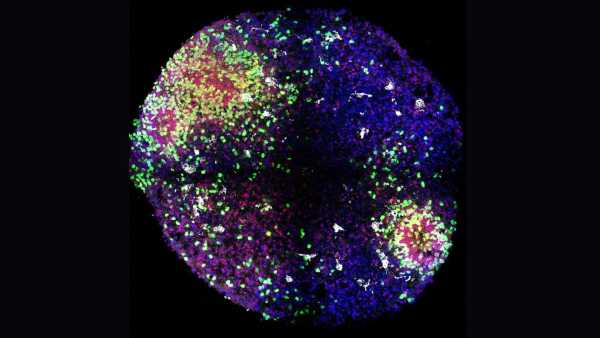

Стикаючись з інфекцією, ці «гуманізовані» миші виробляють імунні клітини, що імітують структуру та різноманітність імунних клітин, що виробляються людьми. Дослідники виявили, що коли їм вводять хімічну речовину, яка викликає поширене запалення в організмі, у мишей розвивається варіант аутоімунного захворювання – вовчака, який дуже схожий на той, що спостерігається у людей.

Після введення людського естрогену миші почали виробляти безліч людських імунних клітин. Серед них були Т-клітини, які безпосередньо атакують мікроби, та В-клітини, що виробляють антитіла, що знищують бактерії та допомагають позначити патогени для знищення.

Щоб побачити, як гуманізовані миші реагують на вакцину, команда ввела тваринам вакцину проти COVID-19, виготовлену компанією Pfizer-BioNTech. У відповідь миші виробили людські антитіла проти коронавірусу SARS-CoV-2. Аналогічно, під час впливу білків бактерії Salmonella typhi, збудника черевного тифу, миші виробляли антитіла проти збудника.